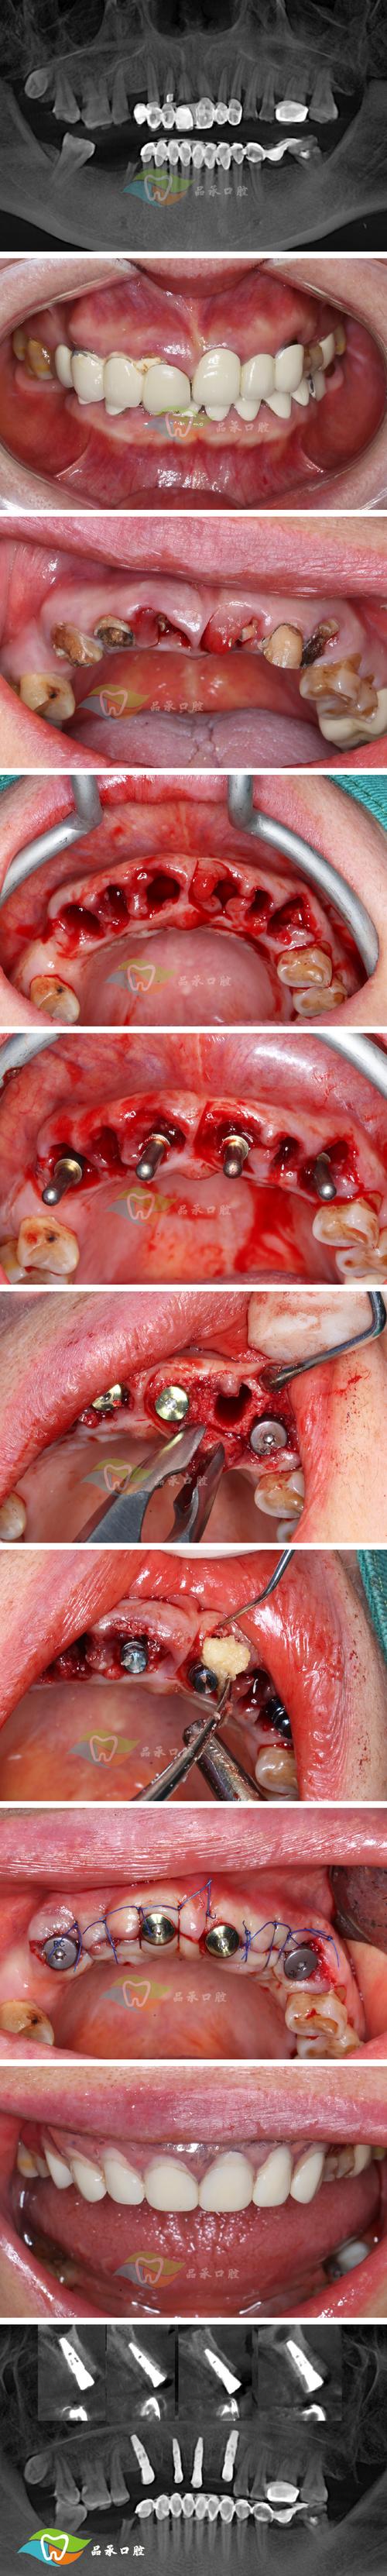

- 锥形束CT(CBCT):可三维重建牙根形态,清晰显示吸收的范围、深度及与牙槽骨的关系,对早期吸收和复杂吸收(如不规则吸收、穿孔)的诊断价值更高,是正畸治疗中监测牙根吸收的重要工具。

- 牙根穿孔:若穿孔较小,可行MTA(矿物三氧化物凝聚体)穿孔修补术;若穿孔过大、牙齿保留困难,需拔除后行种植义齿修复。